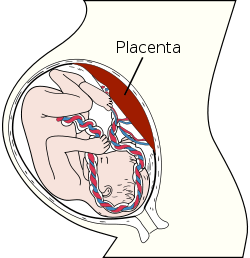

Placenta | |

The placenta (also known as afterbirth) is an organ that connects the developing fetus to the uterine wall to allow nutrient uptake, provide thermo-regulation to the fetus, waste elimination, and gas exchange via the mother's blood supply, fight against internal infection and produce hormones to support pregnancy. The placenta provides oxygen and nutrients to growing babies and removes waste products from the baby's blood. The placenta attaches to the wall of the uterus, and the baby's umbilical cord develops from the placenta. The umbilical cord is what connects the mother and the baby. Placentas are a defining characteristic of placental mammals, but are also found in some non-mammals with varying levels of development.[1] The homology of such structures in various viviparous organisms is debatable and, in invertebrates such as Arthropoda, is analogous at best.

The placenta functions as a fetomaternal organ with two components: the fetal placenta (Chorion frondosum), which develops from the same blastocyst that forms the fetus, and the maternal placenta (Decidua basalis), which develops from the maternal uterine tissue.[4]

Structure

In humans, the placenta averages 22 cm (9 inch) in length and 2–2.5 cm (0.8–1 inch) in thickness, with the center being the thickest, and the edges being the thinnest. It typically weighs approximately 500 grams (just over 1 lb). It has a dark reddish-blue or crimson color. It connects to the fetus by an umbilical cord of approximately 55–60 cm (22–24 inch) in length, which contains two umbilical arteries and one umbilical vein.[5] The umbilical cord inserts into the chorionic plate (has an eccentric attachment). Vessels branch out over the surface of the placenta and further divide to form a network covered by a thin layer of cells. This results in the formation of villous tree structures. On the maternal side, these villous tree structures are grouped into lobules called cotyledons. In humans, the placenta usually has a disc shape, but size varies vastly between different mammalian species.[6]